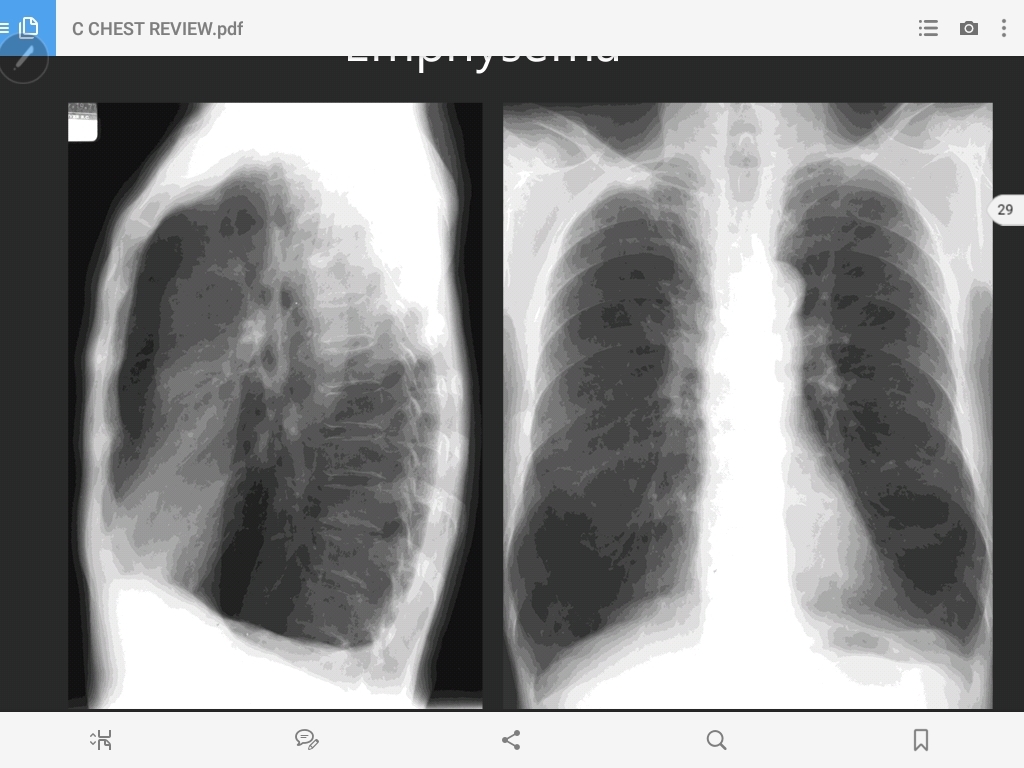

emphysema